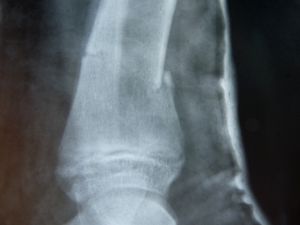

Knochenbruch: Gicht erhöht Risiko nicht (Foto: pixelio.de, Dieter Schütz) |